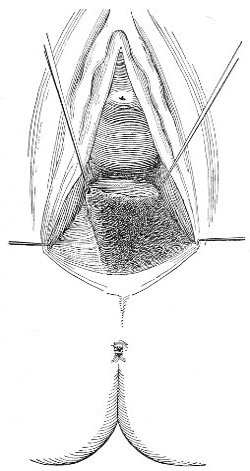

The secondary operation is performed at any time after cicatrization has occurred—often many years after the receipt of the injury. This operation is at present one of the commonest in gynecology, because the injury is not detected, is neglected, or is improperly repaired after labor. In the secondary operation an anesthetic is necessary. The mucous membrane must be removed or denuded on the posterior wall and about the mouth of the vagina, in order that the lacerated structures may be brought again in apposition. The denudation is best made by means of scissors curved on the flat (Figs. 24 and 25).

The strip of mucous membrane to be removed is picked up with a tenaculum (Fig. 26) or with tissue forceps 65 (Fig. 27); the scissors are placed with the blades parallel to the surface to be denuded, and the strip is cut away evenly, in one piece if possible. A similar contiguous strip is removed, and so on until the necessary surface is bare. Sponges in holders (Fig. 28) or continuous irrigation may be used to remove blood.

Silver wire and silkworm gut are the best sutures in the operation of perineorrhaphy.

The suture is conveniently attached to the needle by means of a silk carrier (Fig. 31).

The sutures may be fastened by passing the ends through a perforated shot which is slipped down to the line of union and compressed by the shot-compressor (Fig. 32). All blood should be carefully removed from the surfaces that are brought together. The sutures should only be sufficiently tense to produce accurate apposition. A light gauze drain should be introduced in the vagina, and should be removed in forty-eight hours. Afterward one vaginal douche of about a quart of warm bichloride solution (1:2000) should be administered every day. After the douche the labia should be separated and the vagina carefully dried by cotton held in dressing-forceps. Except in those cases in which the sphincter ani is involved, the bowels may be moved on the second or third day. The woman should stay in bed for two weeks, at the end of which time the sutures should be removed. 67 She should avoid heavy lifting, long standing, and bicycle- or horseback-riding for two months after the operation. Constipation should always be avoided. Coitus may be resumed six weeks after operation.

The special forms of operation will be discussed in the consideration of the varieties of perineal injury.

Slight Median laceration of the Perineum.—In this injury the tear takes place through the fourchette. Posteriorly it may extend as far as the sphincter ani muscle. Upward it may extend for an inch up the posterior vaginal wall. The appearance of this tear is shown in Fig. 33. It will be noted that, as this tear takes place in the median line, none of the muscles that support the perineum are involved, nor are the planes of fascia injured. The perineum is slightly split, and the insertions and origins of the muscles and the fascia are slightly separated. The supporting structures of the perineum and the pelvic floor are, however, uninjured.

Fig. 33.—Recent slight median laceration of the perineum: sutures introduced.

If this tear is detected after labor, it should be closed by the immediate operation. A slight tear involving chiefly the cutaneous aspect of the perineum should be closed by three or four sutures introduced from the outside, as in Fig. 33. The needle should be introduced about a quarter of an inch from the edge of the wound. It should not be passed parallel with the plane of the lacerated surface, but should be swept outward and then inward toward the 68 angle at the bottom of the tear (Fig. 34). It may either emerge at the angle and be re-introduced, or it may be passed directly through to the skin-margin on the opposite side of the wound. If the suture is passed in this way, there will be perfect apposition throughout the whole surface of laceration. If the sutures are improperly passed, there may result only apposition of the skin-edges.

Fig. 34.—Diagram representing the correct and the incorrect method of passing the suture for closure of slight perineal laceration.

If the laceration extends up the posterior vaginal wall, two sets of sutures must be introduced—one on the vaginal aspect of the tear, and one on the skin aspect (Fig. 35).